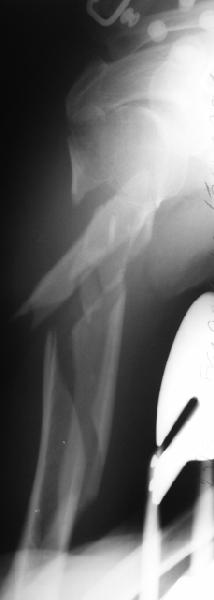

Well, to date he is still on abduction splint with traction applied to a wire placed through the olecranon. Images attached. The acetabulum

was ORIFed. The humerus is still discussing...